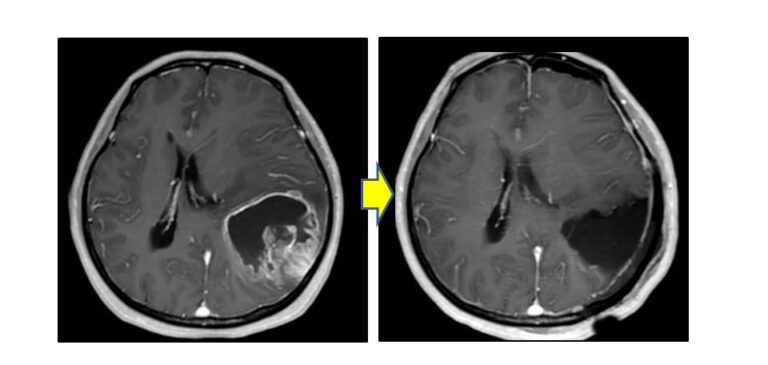

手術

乏突起神経膠腫の治療には、特に腫瘍の悪性度が低い場合、通常、手術が使用されます。ただし、手術では腫瘍を効果的に完全に除去できないことが多いため、再発を避けるために手術後に他の治療法を使用する必要があります。